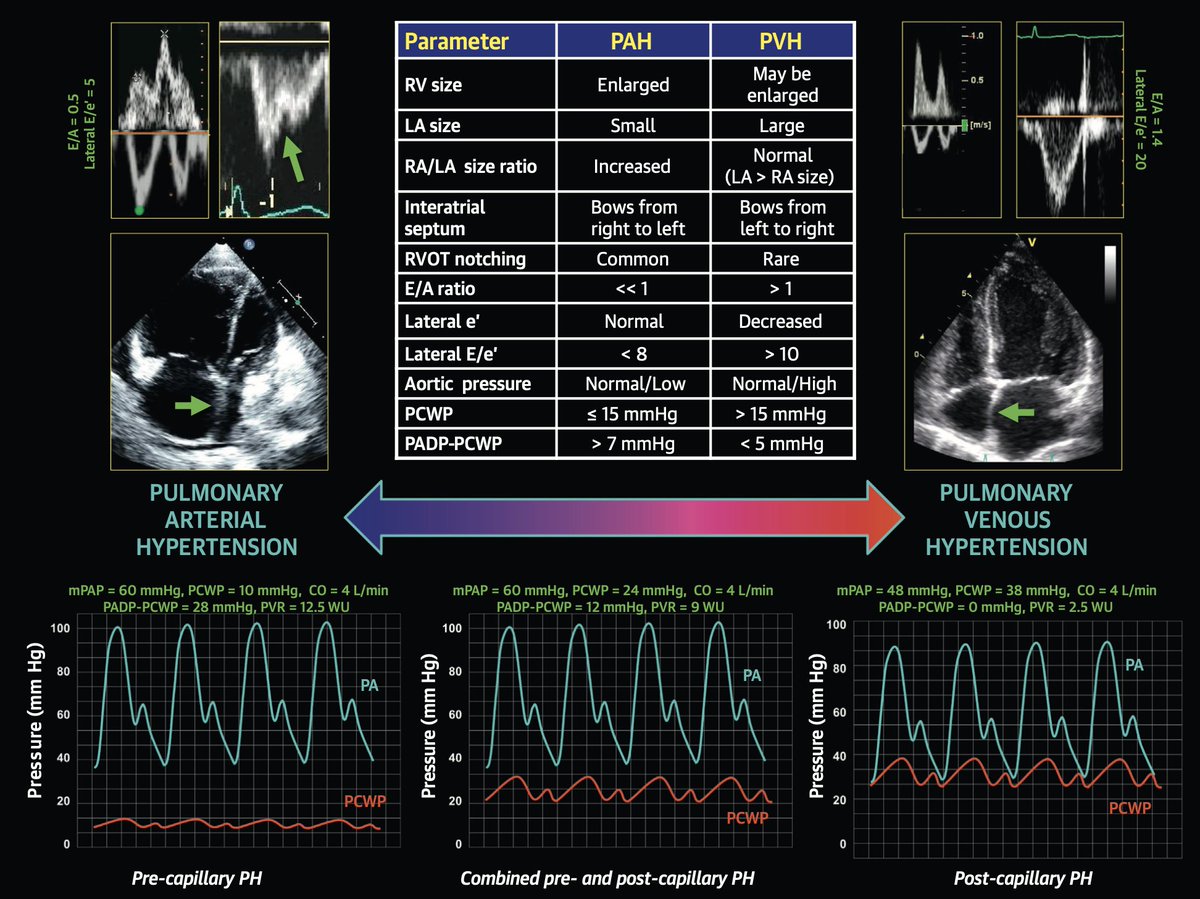

#HFpEF pearl of the day: If a patient with HF symptoms and normal LVEF has E/A ratio < 1 and PA systolic pressure > 50 mmHg on echo, it’s more likely PAH, not HFpEF. Low E/A ratio is due to underfilled LV due to pulmonary vascular obstruction in setting of PAH.

Here is my guide to differentiating PAH vs. CpcPH vs. HFpEF (pulmonary venous hypertension), published here: sciencedirect.com/science/articl…